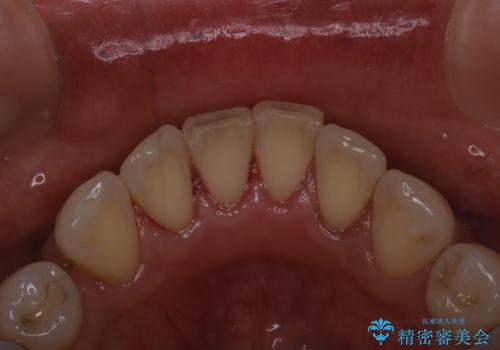

全体の総合的な治療前にPMTC

- 歯科がだいぶ久しぶりで、全額的な治療の前にクリーニングを希望されました。PMTC60分コースを行いました。

歯にステイン(着色)や歯石などが付着していると、汚れなのか虫歯なのかの判別が分かりにくく、正確な診断ができないことがあります。

そのため、治療前には専門的な機械や材料を使用したクリーニング(PMTC)をすることで、ご自身本来の歯の状態となります。より、精密な治療前を行うためには、治療前などにPMTCを行いお口の中の環境を綺麗にすることがおすすめです。